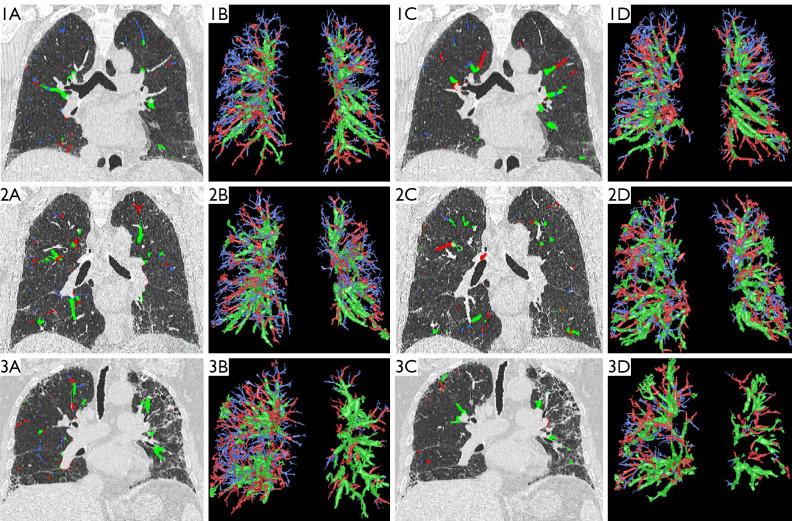

It has recently become possible to quantitatively assess changes in the pulmonary arteries and veins on chest computed tomography (CT) images using automated software tools. The aim of this study was to assess the morphological characteristics of CT-based pulmonary arteries and veins to investigate pulmonary vascular remodeling in connective tissue disease-associated interstitial lung disease (CTD-ILD).

This retrospective study recruited 168 CTD-ILD patients (80 males; mean age, 62±10 years) who underwent standard of care pulmonary function testing (PFT) and CT evaluations. Gender-Age-Physiology (GAP) 1-3 staging was performed on the basis of gender, age, and PFT results. Arterial and venous analyses (volumes, densities, fractions, and tortuosity) were performed using artificial intelligence.

Among the 168 subjects with GAP stage 1 (n=106), stage 2 (n=50), and stage 3 (n=12) who were enrolled, differences in arterial and venous BV5 [volume of pulmonary blood vessels with the cross-sectional area (CSA) less than 5 mm] volume, BV5+ (volume of pulmonary blood vessels with a CSA greater than 5 mm) volume, density and fraction of BV5a/v (BV5 in the pulmonary artery or pulmonary vein) and vascular tortuosity were statistically significant (all P<0.05). The 12 included patients were followed longitudinally for 3-43 months, and the BV5a/v parameters decreased progressively with the worsening of ILD extent and functional impairment. Arterial and venous BV5 volumes, densities, and fractions showed a positive correlation with PFT results (γ=0.179 to 0.608, P<0.05).